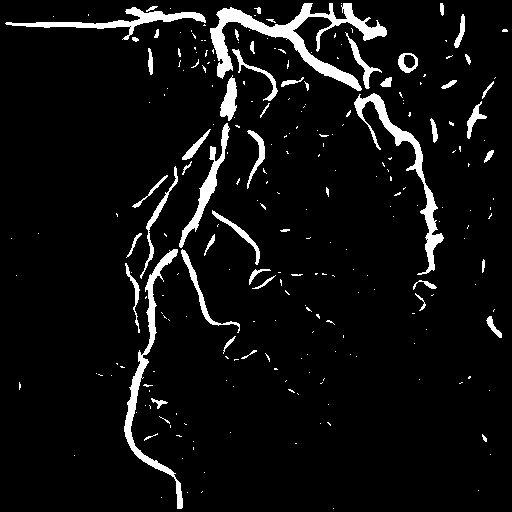

4.1 XACV Dataset

We collect 111 complete records of coronary artery X-ray videos, encompassing the injection, flow through the blood vessels around the heart, and dissipation of the contrast agent. Subsequently, we establish the XACV (X-ray Angiography Coronary Video) dataset. Each video consists of varying numbers of high-resolution coronary artery X-ray images. We invite experienced radiologists to annotate the vascular regions, focusing on one or two frames where the contrast agent is most prominent in each video. The XCAD dataset contains only a single image, and the CADICA video dataset does not provide corresponding ground truth. Therefore, in the following experiments, we conduct all the analyses on our collected XACV dataset and the corresponding GT for each sequence. In Figure 5, we show that compared to other publicly available datasets, XCAD [33] and CADICA [19], our dataset exhibits finer annotations in the vascular regions, providing an advantage for future related tasks. The development and use of our dataset have been approved by our institution’s IRB.